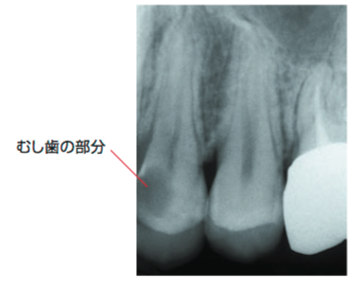

C3

歯の神経やその近くまでむし歯に侵されています 神経が炎症をおこしているので 非常に強い痛みを感じます

虫歯菌(ミュータンス菌)によりエナメル質が溶け神経まで虫歯菌が進行すると神経が炎症を起こし痛みを伴います。症状としては、冷たい物や温かい物がしみる、何もしなくても痛いと感じることがあります(この症状があったからと言って必ず神経を取るわけではありません)。神経まで虫歯が進行しているにもかかわらず治療せずに放置すると、根の先に膿がたまり根の先の顎の骨が溶けることがあります。

全体が、むし歯に侵されています 歯の根の先に膿がたまったり、歯のまわりにも 病気の影響がおよび、歯を残すのがむずかしくなります

歯が虫歯菌により溶けて形が残っていない状態です

ここまでくると歯の痛みはありませんが、歯茎が腫れた痛みや根の先が細菌感染し膿がたまり骨の内部で顎の骨が溶けることがあります。骨が細菌感染し急激に痛みを伴うこともあり虫歯で神経が感染した場合よりも痛みが強いことがあります。